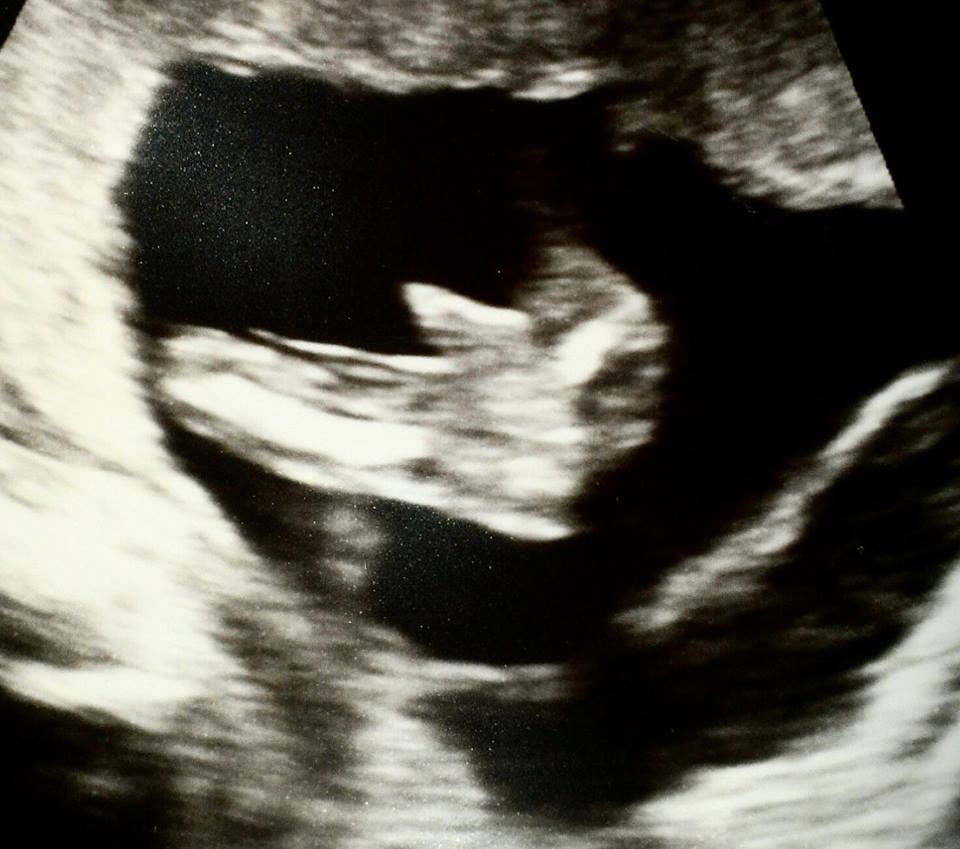

Ultrasound help!

Attachment 18008

I am high risk so had an early anatomy ultrasound. I asked the tech if she was going to tell me the gender but she said it was to early, when she put the wand on my belly it happened to be right between the babys legs and looked like a boy to me, she didn't give any input about what it could be. Could this be cord or is it boy parts? At first I figured it was boy parts but as I look they look a little strange. I was about 15 weeks here, any ideas?

Not enough of the bottom end is captured IMO sorry. Hope the next scan is clearer xx

I am sorry, I suck at this stuff! I am confused, isn't that the bottom of the baby or am I not looking at what I thought I was? I think I am a hopeless case when it comes to looking at these!